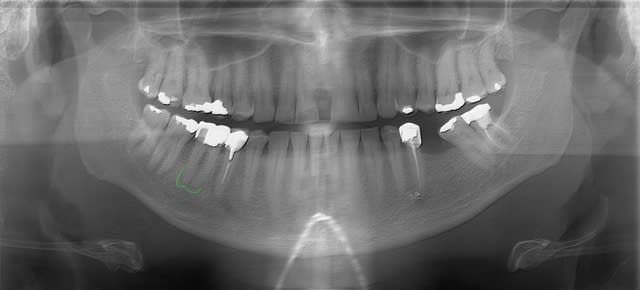

Ce n'est pas une dent dépulpée mais toute la partie occlusale vestibulaire de 17 est plate comme un porte-avion.

Je me suis dit qu'un onlay n'allait jamais tenir dans ces conditions et ai fait la prépa périphérique.

Avez-vous déjà des onlays dans ces conditions qui ont tenu ?

Onlay ou pas   pano dfoqec - Eugenol

Onlay ou pas f6vepj - Eugenol